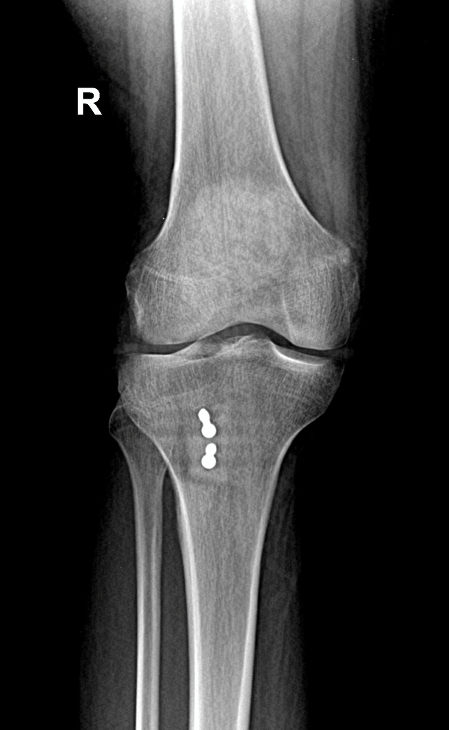

Example X-ray Images

MPFL Reconstruction with Tibial Tubercle Osteotomy